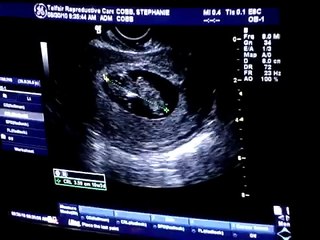

Baby Boy Deruise (21 Week Ultrasound)

Our 21 week ultrasound...